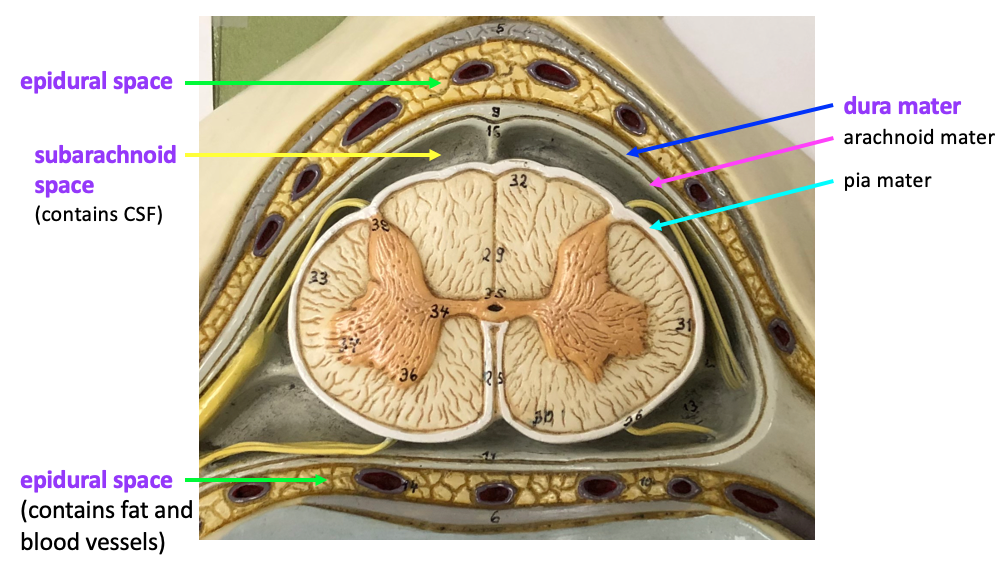

3 meninges:

Dura mater

Arachnoid mater

Pia mater

Epidural

Subarachnoid spaces